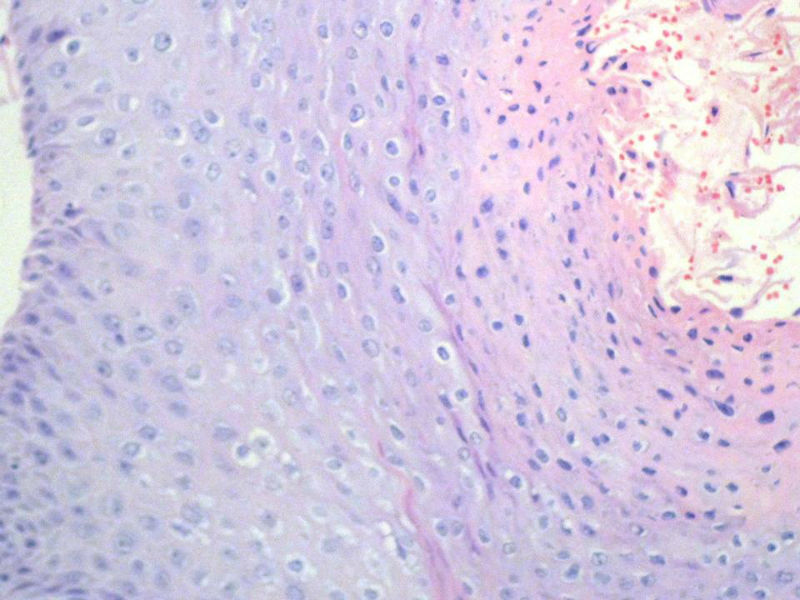

男,72岁,右耳听力下降两个月,检查右外耳道有黄豆大肿物,表面乳头状,手术切除。

乳头状瘤,上皮内可见挖空样细胞,建议HPV检测